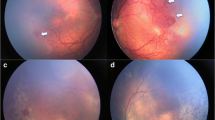

Trinetra Neo (Forus health, Bangalore, India) is a novel low-cost, handheld, light-weight, and portable fundus camera which provides approximately 120° field of view. It uses a light-emitting diode (LED) illumination and a liquid lens-based focusing system. It has been found to be safe for ocular use [17, 18]. This camera has the potential to be used in low-resource countries allowing better telemedicine care (Fig. 5.1).

Comparison of wide-field fundus photographs using the Trinetra neo fundus camera (top panel) showing stage 3 Retinopathy of prematurity (ROP) (a) in the right eye and stage 2 ROP in the left eye (b) in zone II in a preterm infant. Bottom panel shows fundus photographs using the Retcam 3 depicting stage 2 ROP in zone II in right (c) and left eye (d)

The ICON (Phoenix Clinical, Inc., Pleasanton, CA, US) is also a mydriatic, contact, handheld camera with reported improved resolution and color profile for capturing images in dark fundi; Fluorescein Angiography is also available with this device. The Panocam (Visunex Medical Systems, Inc., Fremont, CA, US) is a wireless, contact, handheld camera system with a 130° field of view.